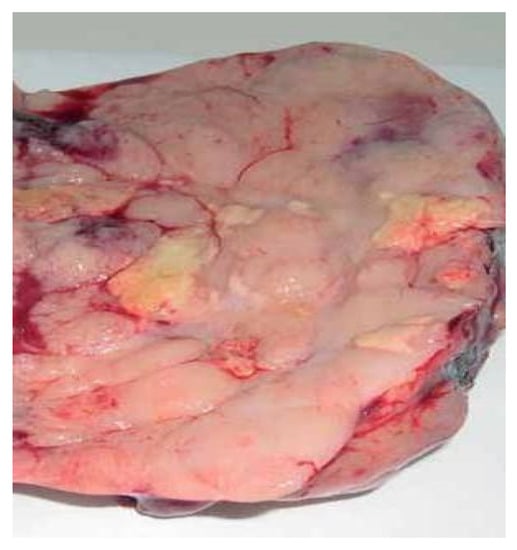

2. Case Presentation